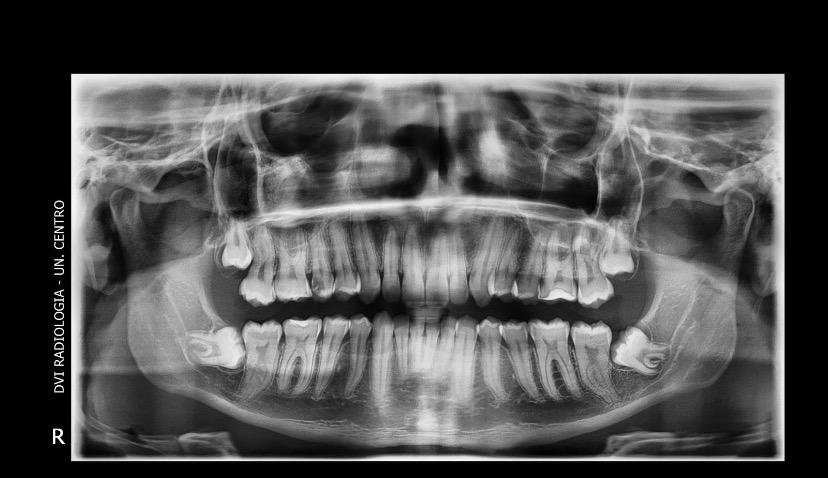

A Patologia Oral e Maxilofacial é a especialidade responsável pelo diagnóstico e tratamento de doenças que afetam a boca, mandíbula e estruturas faciais. Atua na identificação de lesões, cistos e tumores, garantindo diagnóstico preciso e tratamento adequado para preservar a saúde bucal e geral do paciente.